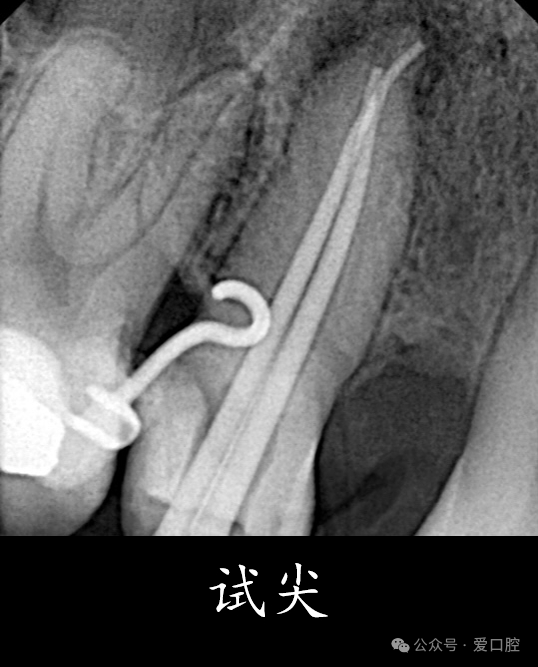

15,安放橡皮障隔离后,显微镜下,开髓,暴露髓腔内牙胶,去除髓腔内牙胶,探查颊侧根管,使用再治疗镍钛锉去除根管上段牙胶,8号k锉,10号k锉疏通至根尖,3%次氯酸钠溶液冲洗,根测长度为19mm,3%次氯酸钠溶液冲洗,探查腭侧根管,发现髓室顶未揭干净,有牙胶残留,揭净髓室顶,去净残留牙胶,疏通腭侧根管至根尖,3%次氯酸钠溶液冲洗,根测长度为19mm,镍钛预备至3504,试尖, 3%次氯酸钠溶液冲洗, Eddy荡洗(20秒3次),蒸馏水冲洗,17%EDTA溶液冲洗,蒸馏水置换,吸干,氢氧化钙封药,玻璃离子暂封。